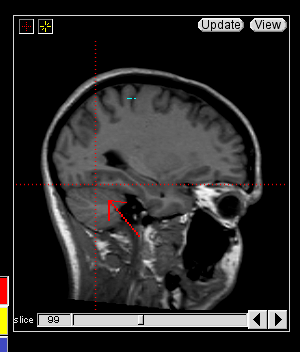

The insular cortex is “hidden” between the temporal and inferior parietal corticies. By drawing sulci lines in the sagittal view, we gain an outline of it in the coronal. Choose a sagittal slice where insula is clearly visible (Fig 1), then draw a “circle” around it (Fig 2). Do this for several slices and for both hemispheres.

Figure 1              Figure

2